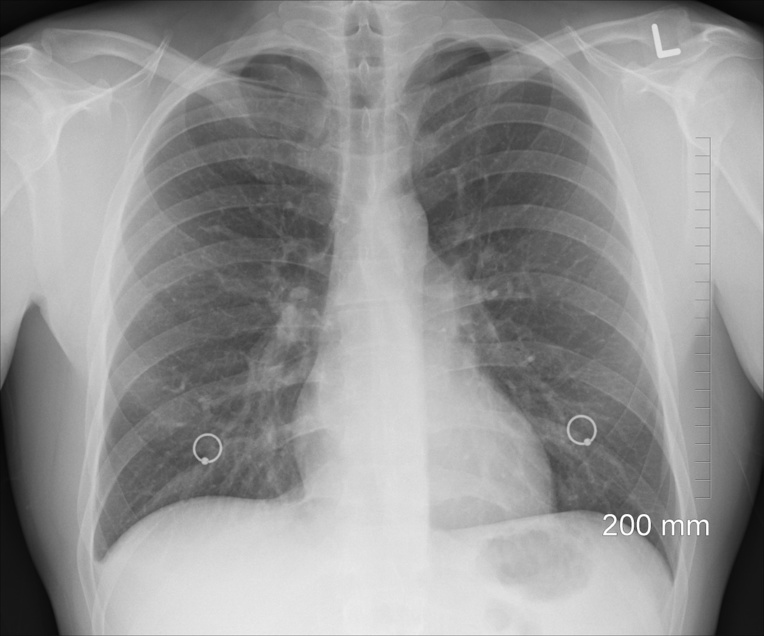

Dans les formes infectieuses les plus graves, "quand on découvre que l'aspergillus est en cause, le poumon commence à se détruire, il y a d'énormes cavités avec des boules de champignons à l'intérieur", explique le docteur Godet.